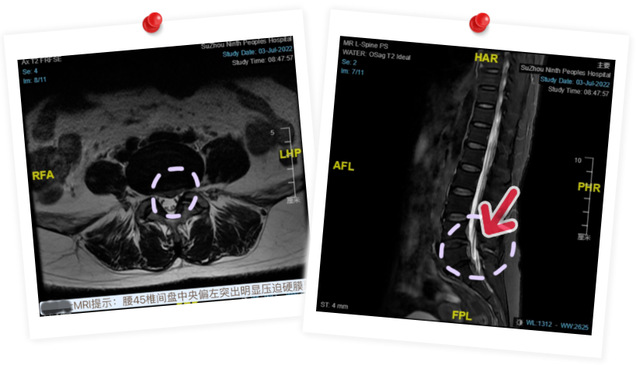

患者沈女士在入院2天前突发会阴部麻木及双下肢麻木无力,当时未予重视,直至小便不能自解,腹部膨隆才来院就诊。经入院进一步检查,被诊断为“马尾综合征”。

骨科主任言湛军介绍,“马尾综合征”是腰椎间盘突出、腰椎管狭窄、腰椎外伤或肿瘤等原因引起的一种临床表现,往往提示神经功能严重受损,耽误越久,神经功能恢复状况越严峻。因此,出现“马尾综合征”必须在确保患者生命安全的前提下尽早进行手术。